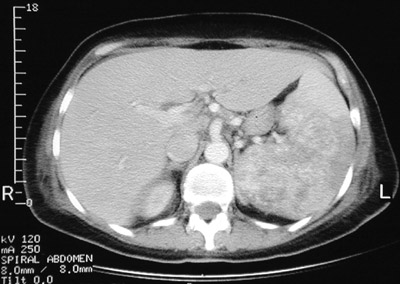

| There is a heterogenous splenic mass seen in the abdominal CT scan above. This large mass expands the spleen. Histologically, it was an angiosarcoma. In the T1 weighted MRI scan below can be seen areas of increased signal intensity characteristic for hemorrhage in a vascular neoplasm. A T2 weighted MRI scan is shown at the bottom in which the hemorrhagic-vascular areas appear darker. |